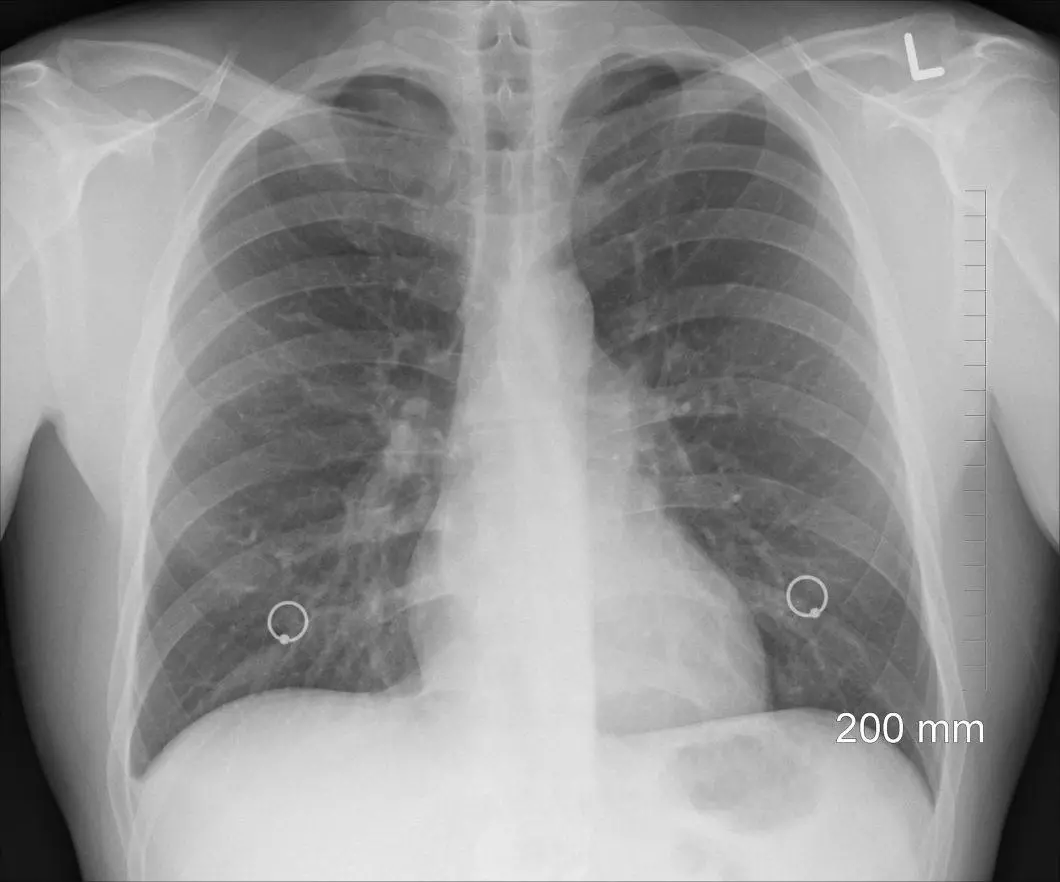

Ce schéma dessin montrent l'organisation des poumons de l'homme (3 lobes à droite, deux lobes à gauche) et la trachée....